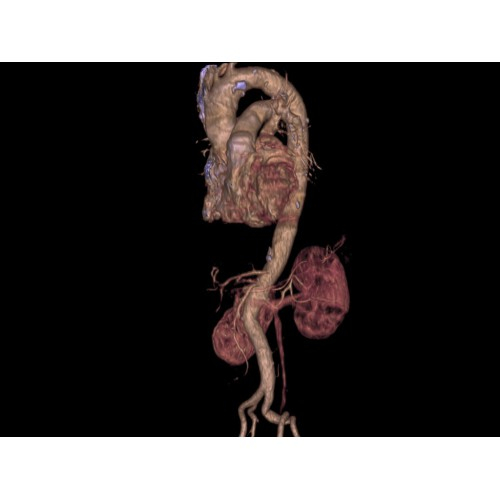

Позволяет проводить комплексные исследования всех анатомических зон, включая нейровизуализацию, ангиографию, исследования органов грудной и брюшной полости. Особенно эффективен для раннего выявления онкологических заболеваний.

Специализированные исследования